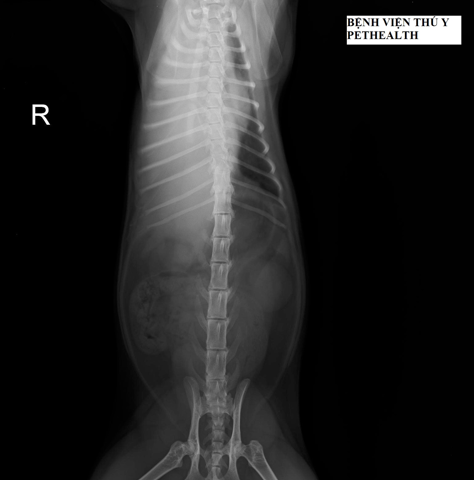

Tràn dịch màng phổi thường được chẩn đoán bằng cách chụp X quang (X-quang) của ngực. Có một số phát hiện đặc trưng trên X quang sẽ giúp bác sĩ thú y của bạn xác định sự hiện diện của tràn dịch màng phổi. Trong một số trường hợp, siêu âm cũng có thể được sử dụng để xác định tràn dịch màng phổi. Đây là một kỹ thuật đặc biệt hiệu quả khi chỉ có một lượng nhỏ tràn dịch màng phổi.